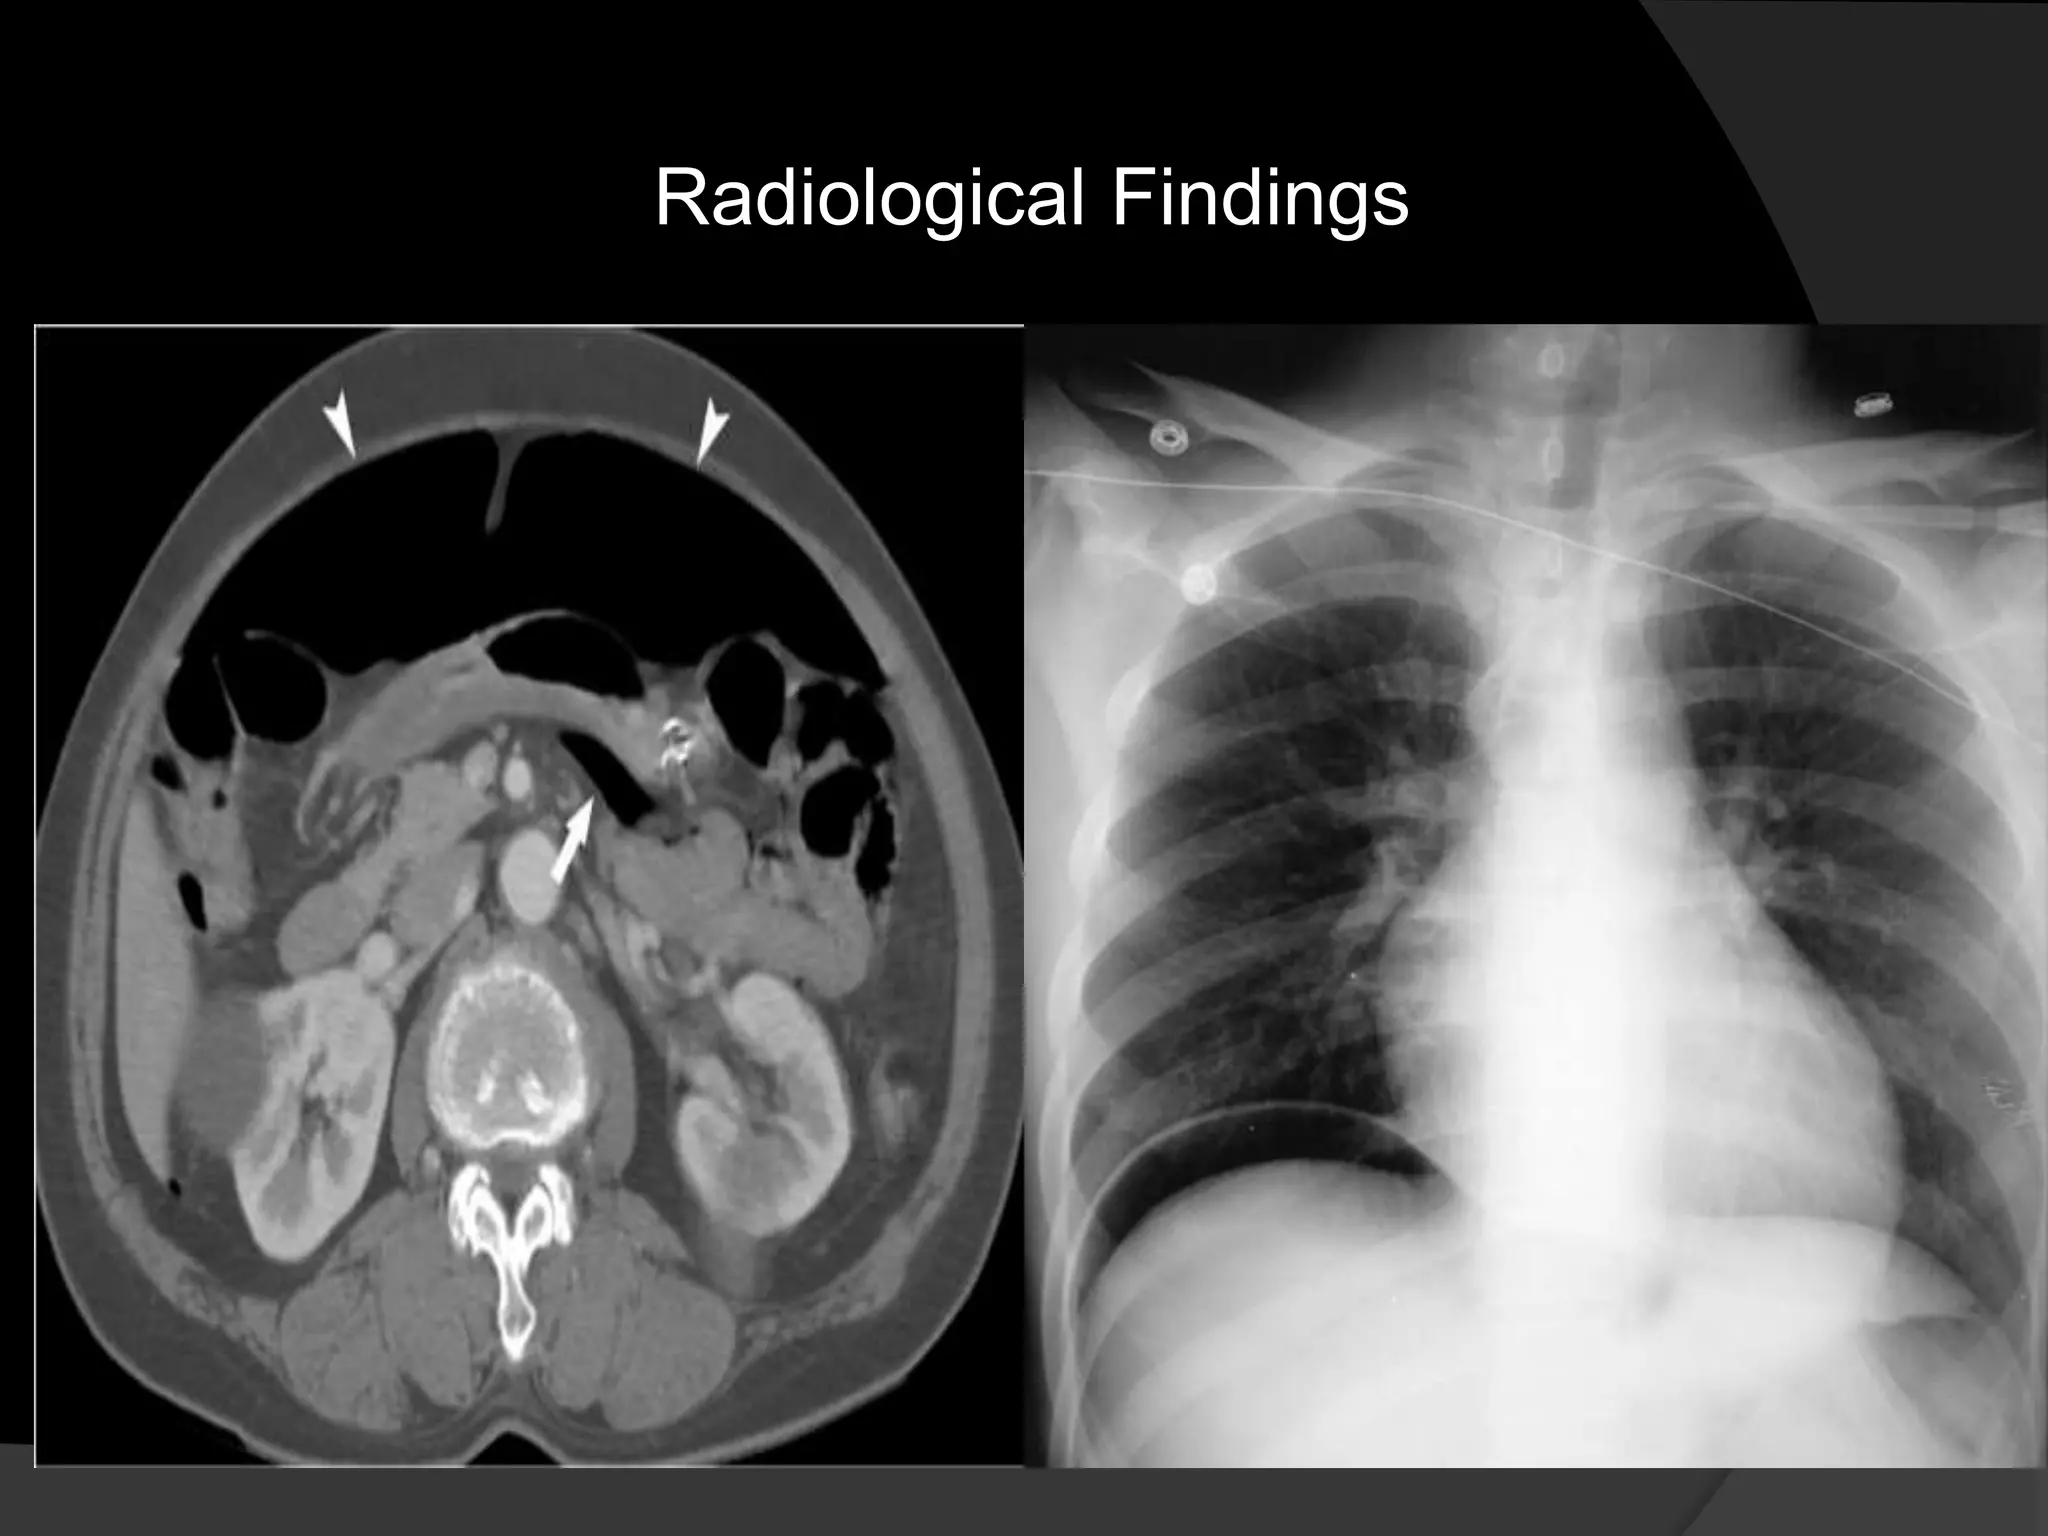

Lymphoma

NHL located in the small bowel mesentery

NHL is the most

common cause of

lymphadenopathy.

Usually there are other

sites with lymphoma.

The CT attenuation at

diagnosis is very

homogeneous in most

cases with minimal to

no enhancement.

Heterogeneous

attenuation is seen

only in cases with

aggressive histology.

During treatment the

attenuation becomes

heterogeneous as a

result of necrosis and

fibrosis.

Calcification may

occur.